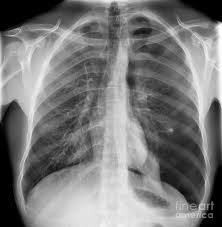

Chest X Ray Showing Large Right Pneumothorax With Collapsed Lung Download Scientific Diagram from www.researchgate.net Jul 02, 2021 · a collapsed lung occurs when air escapes from the lung. Air can enter the pleural space by two mechanisms, either. Now with integrated gestational age calculator and decision support (e.g., retinopathy of prematurity, rsv prophylaxis). Search only for pneumothorax x ray It occurs when air accumulates between the parietal and visceral pleurae inside the chest. The air accumulation can apply pressure on the lung and make it collapse. The degree of collapse determines the clinical presentation of pneumothorax. This buildup of air puts pressure on the lung, so it cannot expand

It occurs when air accumulates between the parietal and visceral pleurae inside the chest. Nov 16, 2020 · a pneumothorax is defined as a collection of air outside the lung but within the pleural cavity. The air accumulation can apply pressure on the lung and make it collapse. The degree of collapse determines the clinical presentation of pneumothorax. Search only for pneumothorax x ray The air then fills the space outside of the lung, between the lung and chest wall. Air can enter the pleural space by two mechanisms, either. Now with integrated gestational age calculator and decision support (e.g., retinopathy of prematurity, rsv prophylaxis). Aug 11, 2021 · fenton 2013 growth calculator for preterm infants. This buildup of air puts pressure on the lung, so it cannot expand Jul 02, 2021 · a collapsed lung occurs when air escapes from the lung.